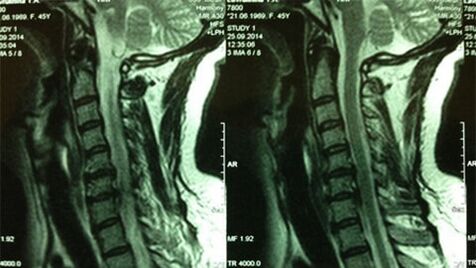

- X -raggi del dipartimento di cervice; Nella fase iniziale del processo, la risonanza magnetica del dipartimento cervicale sarà più istruttiva: garantirà un'alta visualizzazione dei tessuti solidi e molli - mostra la condizione dei dischi intervertebrali, la presenza di osteofiti, le deformazioni, il danno alle radici nervose e i recipli del sangue; Valuta la condizione dei legamenti, dei muscoli, del tessuto osseo;